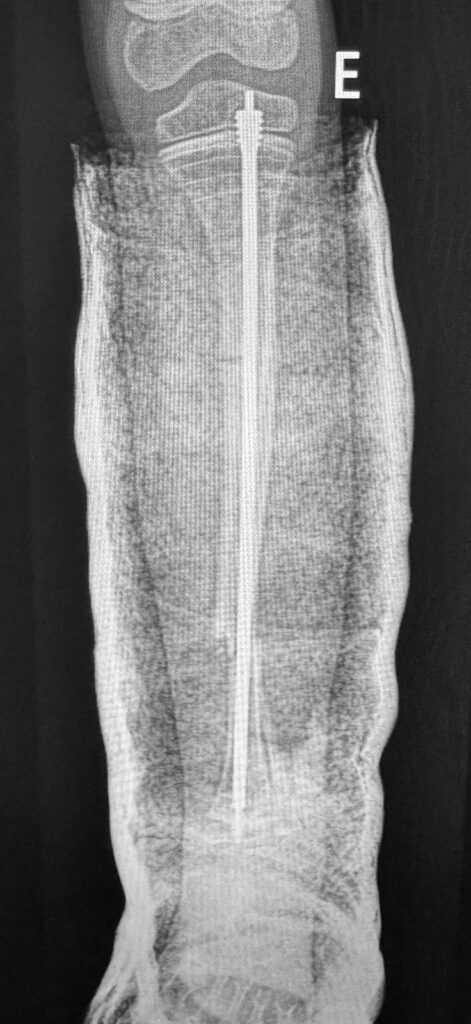

O paciente, que sofria de múltiplas fraturas recorrentes e apresentava uma grave deformidade na perna esquerda, foi tratado com a implantação de uma haste intramedular telescopada Fassier-Duval. Esse dispositivo, que se ajusta ao crescimento do osso, oferece suporte e estabilidade, prevenindo fraturas à medida que a criança cresce.

Apesar da complexidade do procedimento, devido à fragilidade óssea característica da doença, a cirurgia foi um sucesso. O pós-operatório foi tranquilo, com alta no dia seguinte e imobilização gessada simples. A criança iniciará fisioterapia nas próximas semanas.